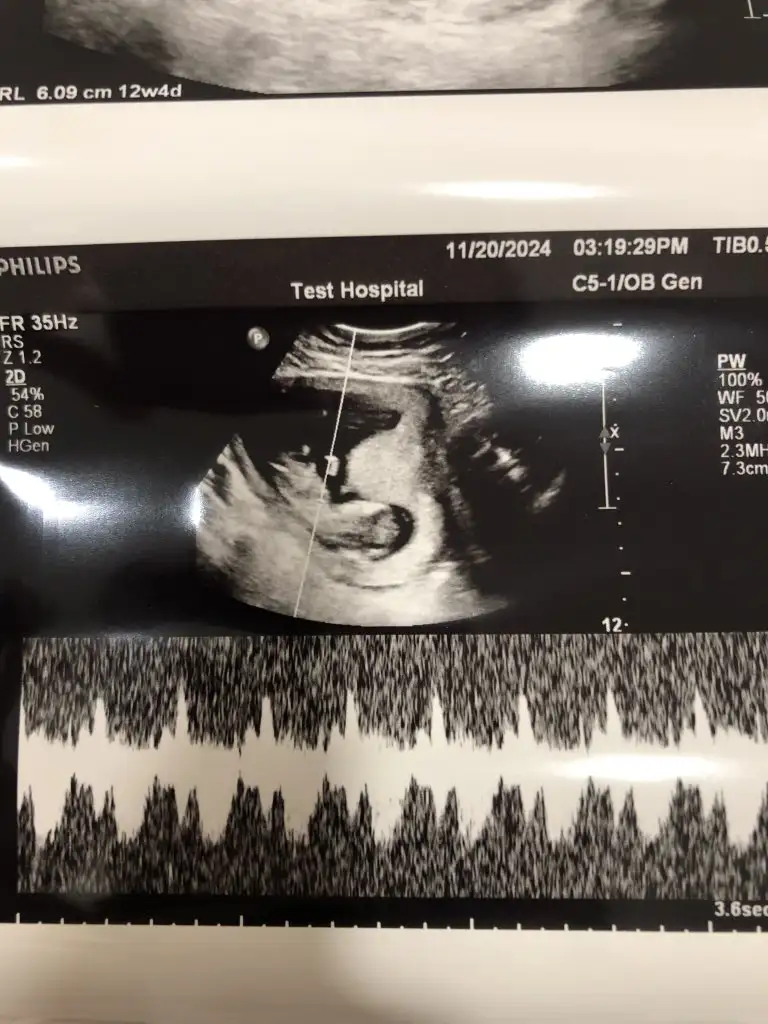

Banada bakabilirminiz 13 haftalık

• IMG_20241117_072114.webp

IMG_20241117_072114.webp

20,7 KB · Görüntüleme: 50

Bana da bakar mısınız sanki çıkıntı yukarı çıkıyor gibi erkeğe benzettim ama düz de değil tam. Daha erken mi acaba kafa yapısı erkek gibi

Eklentiler

• IMG_5349.webp

IMG_5349.webp

48,4 KB · Görüntüleme: 52

• IMG_5348.webp

IMG_5348.webp

30 KB · Görüntüleme: 46

• IMG_5347.webp

IMG_5347.webp

30,3 KB · Görüntüleme: 51